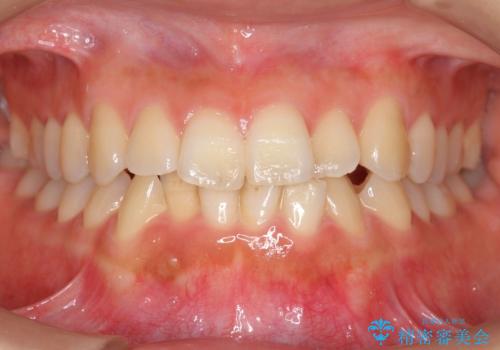

[40代男性・受け口] 下のみ抜歯の矯正治療

- 前歯の反対咬合を主訴に来院。

歯の数を揃えて下の前歯を下げるため、下を二本抜歯して並べました。

時間は多少かかりましたが、治療結果には大変満足していただきました。

40代男性ということもあり、なかなか下の臼歯が動かず隙間を閉じるのが大変でしたが、無事治療を終えることができました。